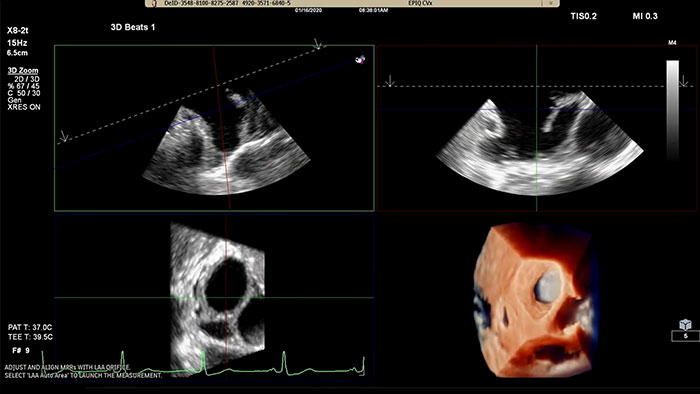

左心耳を迅速・簡単に、直感的に評価するには EPIQ CVx Transcend の LAA ソリューションについて

3D Auto LAA で LAA オリフィス測定を迅速に取得